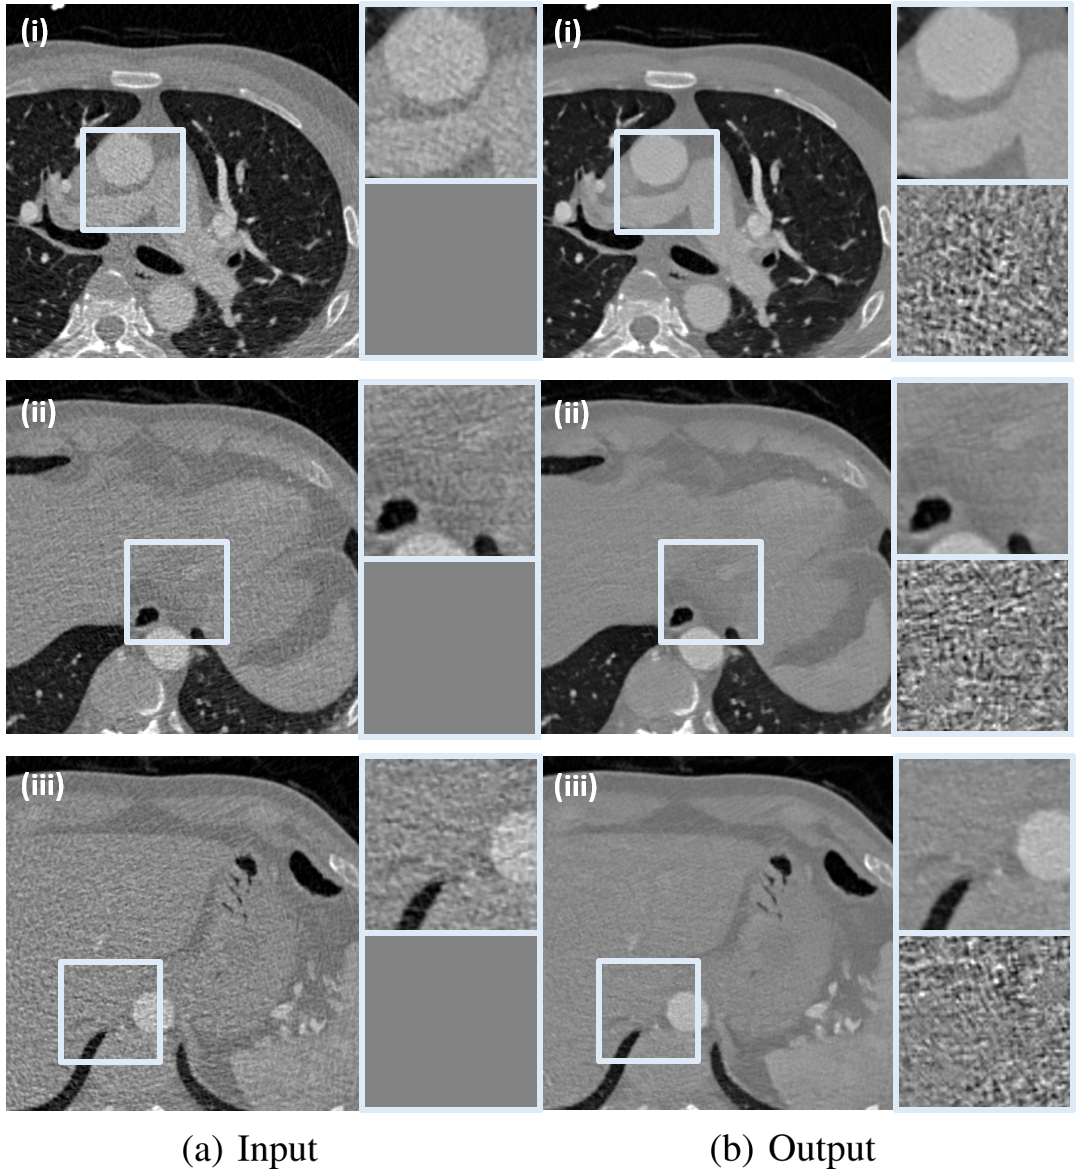

In Fig. 10, there are three representative denoising results by the proposed CycleGAN with an invertible generator to verify the noise reduction performance qualitatively. The gray boxes in the input low-dose CT images and the denoising result images are enlarged in order to more accurately visualize the noise reduction performance, and their difference from the input are also visualized. The difference images clearly show the removed noise components. As can be seen from Fig. 10, the proposed method removes noise components evenly without any structural information loss. Therefore, it distinguishes bone and each soft tissue more clear.

Also, Fig. 12 shows three representative denoising results by the proposed cycle-free CycleGAN with an invertible generator. The gray boxes in the low-dose inputs and denoised outputs are enlarged. The proposed method properly removes noise components from input low-dose CT images, so that each soft tissue in the resulting denoised images is distinguished clearly.